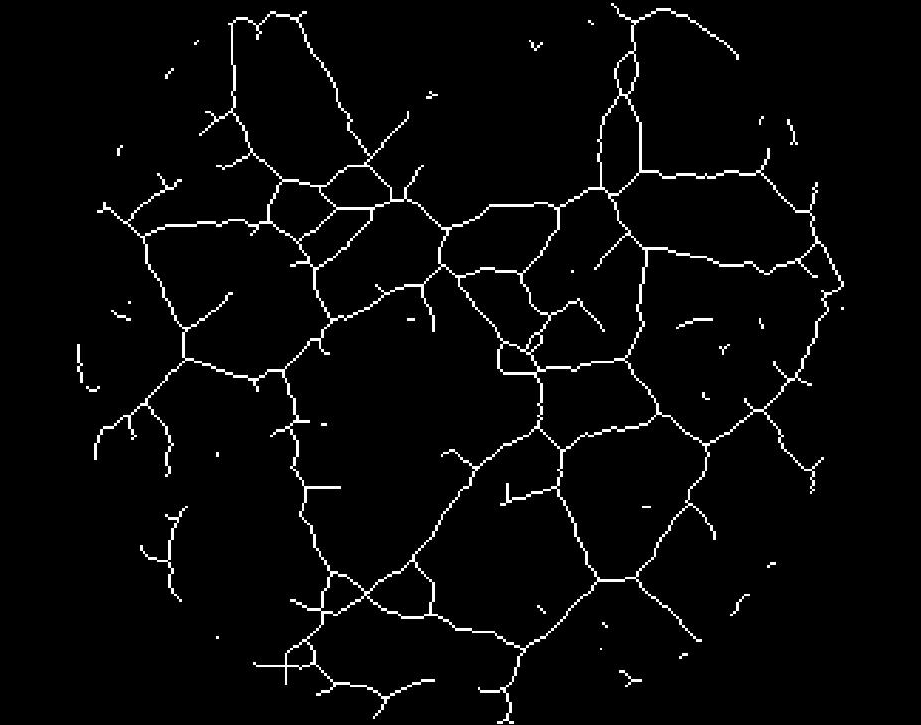

El siguiente procedimiento es aplicar un proceso de binarización (ver Fig.11), seguido de otro de esqueletonización (ver Fig.12), de forma que quedan perfectamente delineados los canales detectados. En la figura 13 se puede observar la superposición de la imagen resultantes del pre-procesamiento (paso 1) y del procesamiento (paso 2); se marcan en negro los canales conectados y en blanco los canales aislados (no conectados).

![]()

Figura 11. Binarización Figura 12. Esqueletonización

3) El post-procesamiento final se encarga de analizar la imagen binaria/esqueleto resultante para la extracción de los siguientes parámetros: número de nodos, canales conectados/no conectados y sus longitudes, longitud media de los canales conectados y no conectados y área total analizada. Los canales de escape, es decir, aquellos que se pierden en el borde del área de trabajo, se consideran conectados si superan un umbral de longitud predeterminado.

Figura 13. Superposición de imagen con trazado de canales detectados.